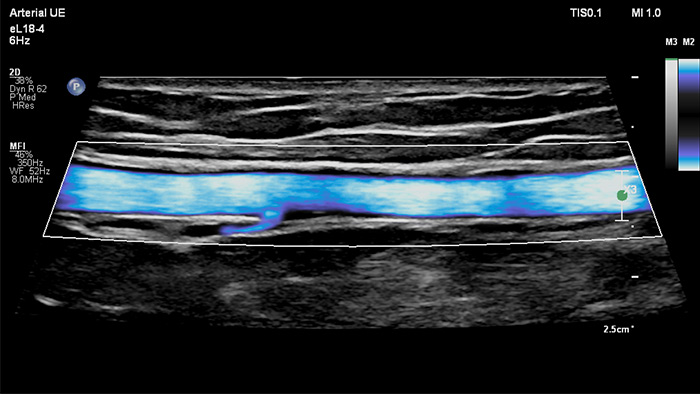

Philips MicroFlow Imaging è concepito per rilevare con considerevole sensibilità il flusso di sangue lento e debole nei tessuti e migliorare la risoluzione del flusso in esami vascolari. Grazie alla risoluzione elevata e agli artefatti ridotti al minimo, i medici sono in grado di visualizzare e caratterizzare piccole alterazioni del flusso attorno alla placca stenotica per formulare diagnosi affidabili.